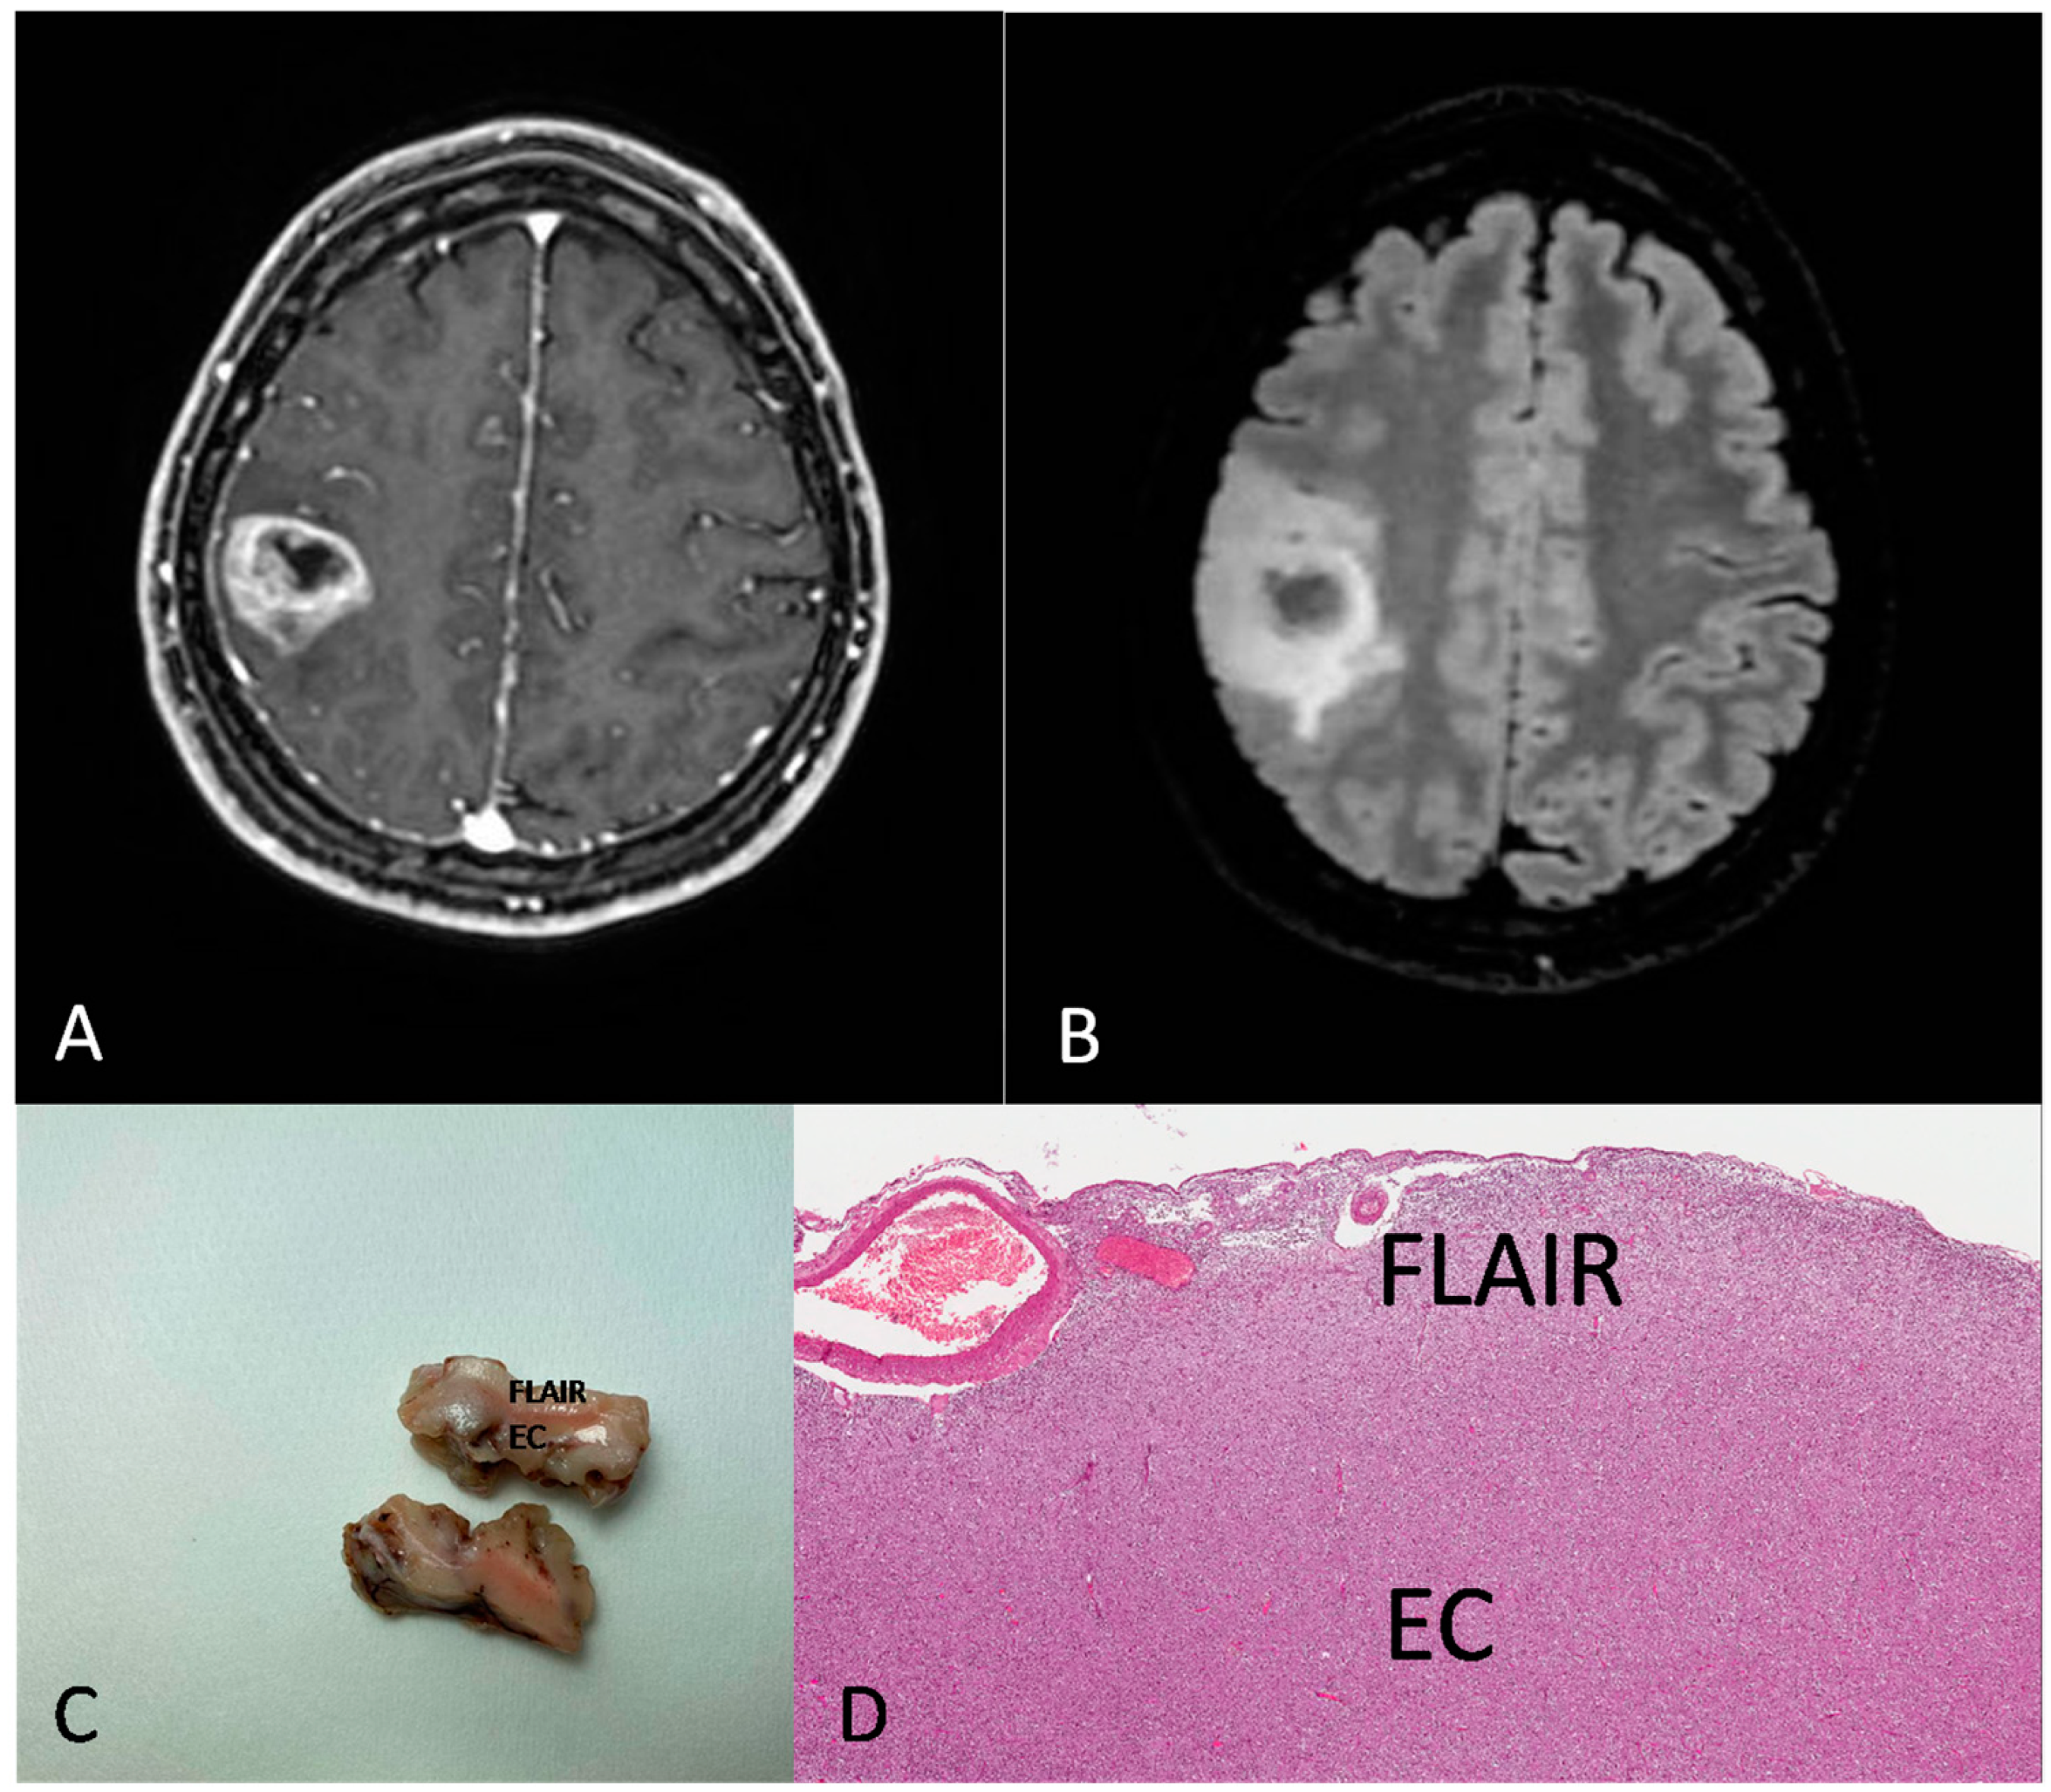

Figure 3.

Preoperative MRI from a 31-year-old woman. (A) Axial section of a T1-weighted sequence with gadolinium showing a rolandic tumor with necrotic core and ring enhancement. (B) FLAIR sequence showing a hyperintensity beyond the EC. (C,D) Gross image (C) and histological medium magnification (D) showing both EC and FLAIR region from the excised mass ((D) H&E; original magnification 50×).